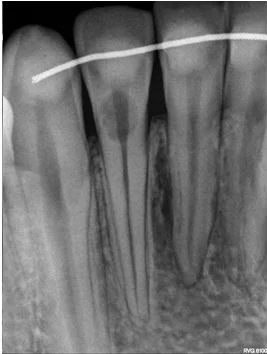

11. What is the radiolucency on the teeth # 1.1, 1.2, 1.3?

12. What is the condition showed by the arrow?

13. What condition can be seen on the teeth # 4.4 and 4.5?

14. What condition can be seen on the root surface of tooth # 1.1.?